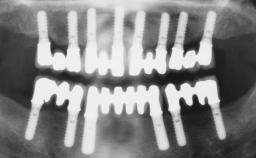

Immediate Loading of Six Implants in the Maxilla and Final Restoration with a Full-Arch Gold/Ceramic FDP Involving the Concept of Tilted Implants

# of Implants 6

Type of Implants One-Piece|Reduced-Diameter

Defining Characteristics Fully edentulous upper jaw to be rehabilitated with four or more implants

Modality Fixed hybrid bridge on 5+ implants

Bone Volume Deficient horizontally, allowing simultaneous augumentation